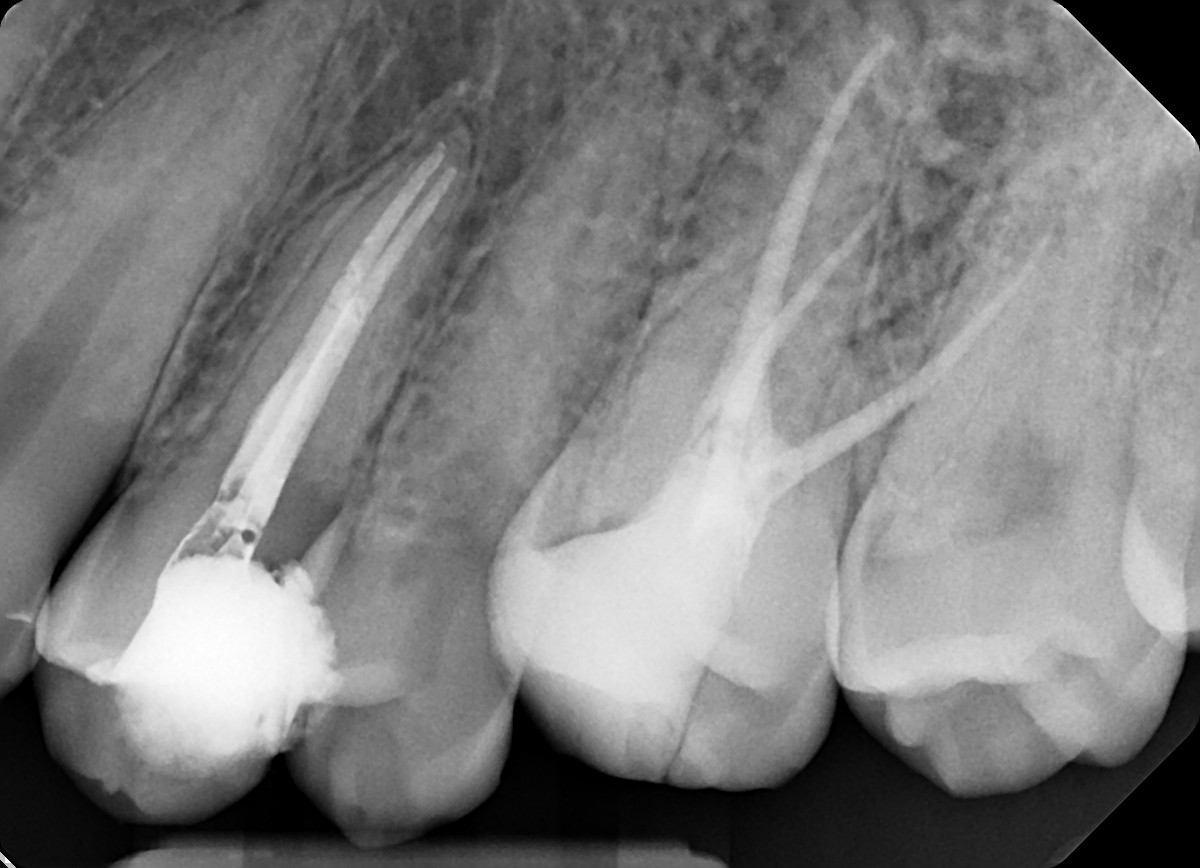

3. Evaluate the root canal treatment of tooth # 1.7?